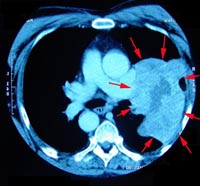

Phương pháp thâm nhập huyết quản là một trong những phương pháp trị liệu ung thư tiên tiến nhất hiện nay, và đang được ngày càng nhiều quốc gia phát triển trên thế giới coi trọng. Phương pháp này làm thay đổi lộ trình dẫn thuốc truyền thống, tiêm thuốc trực tiếp vào khối u, nâng cao nồng độ thuốc lên nhiều lần làm tăng hiệu quả điều trị và giảm tác dụng phụ của trị liệu hóa chất.

Khối u sinh ra trong cơ thể con người cũng có động mạch và tĩnh mạch, chúng tiếp nhận chất dĩnh dưỡng để tồn tại và di chuyển thông qua hệ thống tuần hoàn máu. Phương pháp trị liệu thâm nhập huyết quản được tiến hành thông qua một ống dẫn rất nhỏ, đưa từ động mạch chủ dưới bẹn đi vào cơ thể, dưới định vị của hệ thống giám sát DSA, ống dẫn có thể được đưa bào các bộ phận của cơ thể, thông qua mà hình sẽ thấy vị trí khối u và di chuyển vào động mạch của khối u. Sau khi ống dẫn được đưa vào động mạch của khối u, các loại thuốc có thể thông qua ống dẫn này để truyền trực tiếp vào khối u hoặc khu vực cần trị liệu, các loại thuốc này bao gồm cả Đông y và Tây y. Nếu trong thuốc có hóa chất thì các hóa chất sẽ được đưa trực tiếp vào khối u, giết chết tế bào ung thư với nồng độ cao và đem lại hiệu quả rõ rệt, phương pháp này cũng được gọi là “phương pháp trị liệu hóa chất cục bộ”, phương pháp này có thể giảm thiểu tối đa tác dụng phụ gây hại cho cơ thể người bệnh.

Ống dẫn khi đưa vào động mạch còn có thể dẫn chất làm tắc động mạch của khối u, khiến khối u mất đi nguồn cũng cấp dinh dưỡng và bị “bỏ đói”, phương pháp này được gọi là “trị liệu nút mạch”. Có thể làm nút mạch được hay không chủ yếu còn phụ thuộc vào điều kiện của các động mạch của khối u, cũng phụ thuộc vào trình độ thao tác và kinh nghiệm của bác sỹ.

Đặc điểm của trị liệu thâm nhập huyết quản

Phương pháp truyền thông là truyền thuốc qua tĩnh mạch, thuốc được đưa đến toàn cơ thể, nồng độ của thuốc tác động đến khối u cũng phải điều chỉnh để không tác động quá mức đến các cơ quan lành lặn khác của cơ thể, vì vậy việc điều trị kết quả vẫn còn hạn chế và tác dụng phụ lại tương đối lớn. Thực hiện trị liệu qua thâm nhập huyết quản, thuốc được trực tiếp vào khu vực có khối u thông qua động mạch chủ, nồng độ thuốc có thể cao gấp nhiều lần so với thông thường, tác dụng tiêu diệt khối u cao. Tuy nhiên lại không gây ảnh hưởng nhiều đến các tổ chức lành lặn khác, do đó có thể nâng cao hiệu quả điều trị mà giảm tối đa tác dụng phụ cho toàn cơ thể. Trị liệu thâm nhập huyết quản có thể truyền thuốc làm tắc động mạch “bỏ đói” tế bào ung thư, đây là phương thức đặc biệt nhất của trị liệu thâm nhập huyết quản, nó góp phần không nhỏ trong trị liệu ung thư.